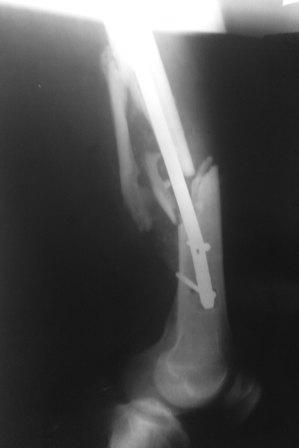

Большое спасибо за ответы. Прошу прощения, что сразу не показал боковую проекцию (прилагаю сейчас). Может быть с таким торцевым упором не производить динамичсекую фиксацию, а провести динамизацию позже.

Да, такая картина заставляет план подкорректировать. После удаления стержня надо дистрактором одномоментно или, если не получится, постепенно восстановить длину. И для окончательного устранения антекурвации надо взять гвоздь потолще и подлиннее.

Уважаемый коллега. Боковая проекция еще раз свидетельствует о том, что в плане стабильности и биомеханики оптимальным будет ретроградный синтез с предварительным наложением дистрактора или применения ортопедической приставки, при этом нет необходимости вскрывать зону перелома, мне кажется имеюшийся угол искривления атакующего конца стержня позволит без технических трудностей её удалить. При отсуствии гибких риммеров антеградный реостеосинтез будет проблематичным, в плане блокировки теперь уж статическая фиксация оптимальна.